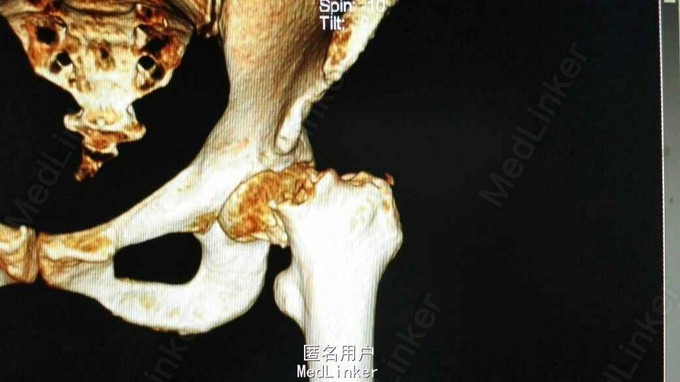

左下肢外旋30度、短锁2cm 畸形,左髋部压痛、左下肢轴向叩击痛(+),左髋部主动活动受限 髋关节正侧位片及骨盆CT提示左股骨颈头下型骨折

诊断:左股骨颈骨折(头下型,Garden IV期) 治疗:闭合牵引复位开心钉内固定术